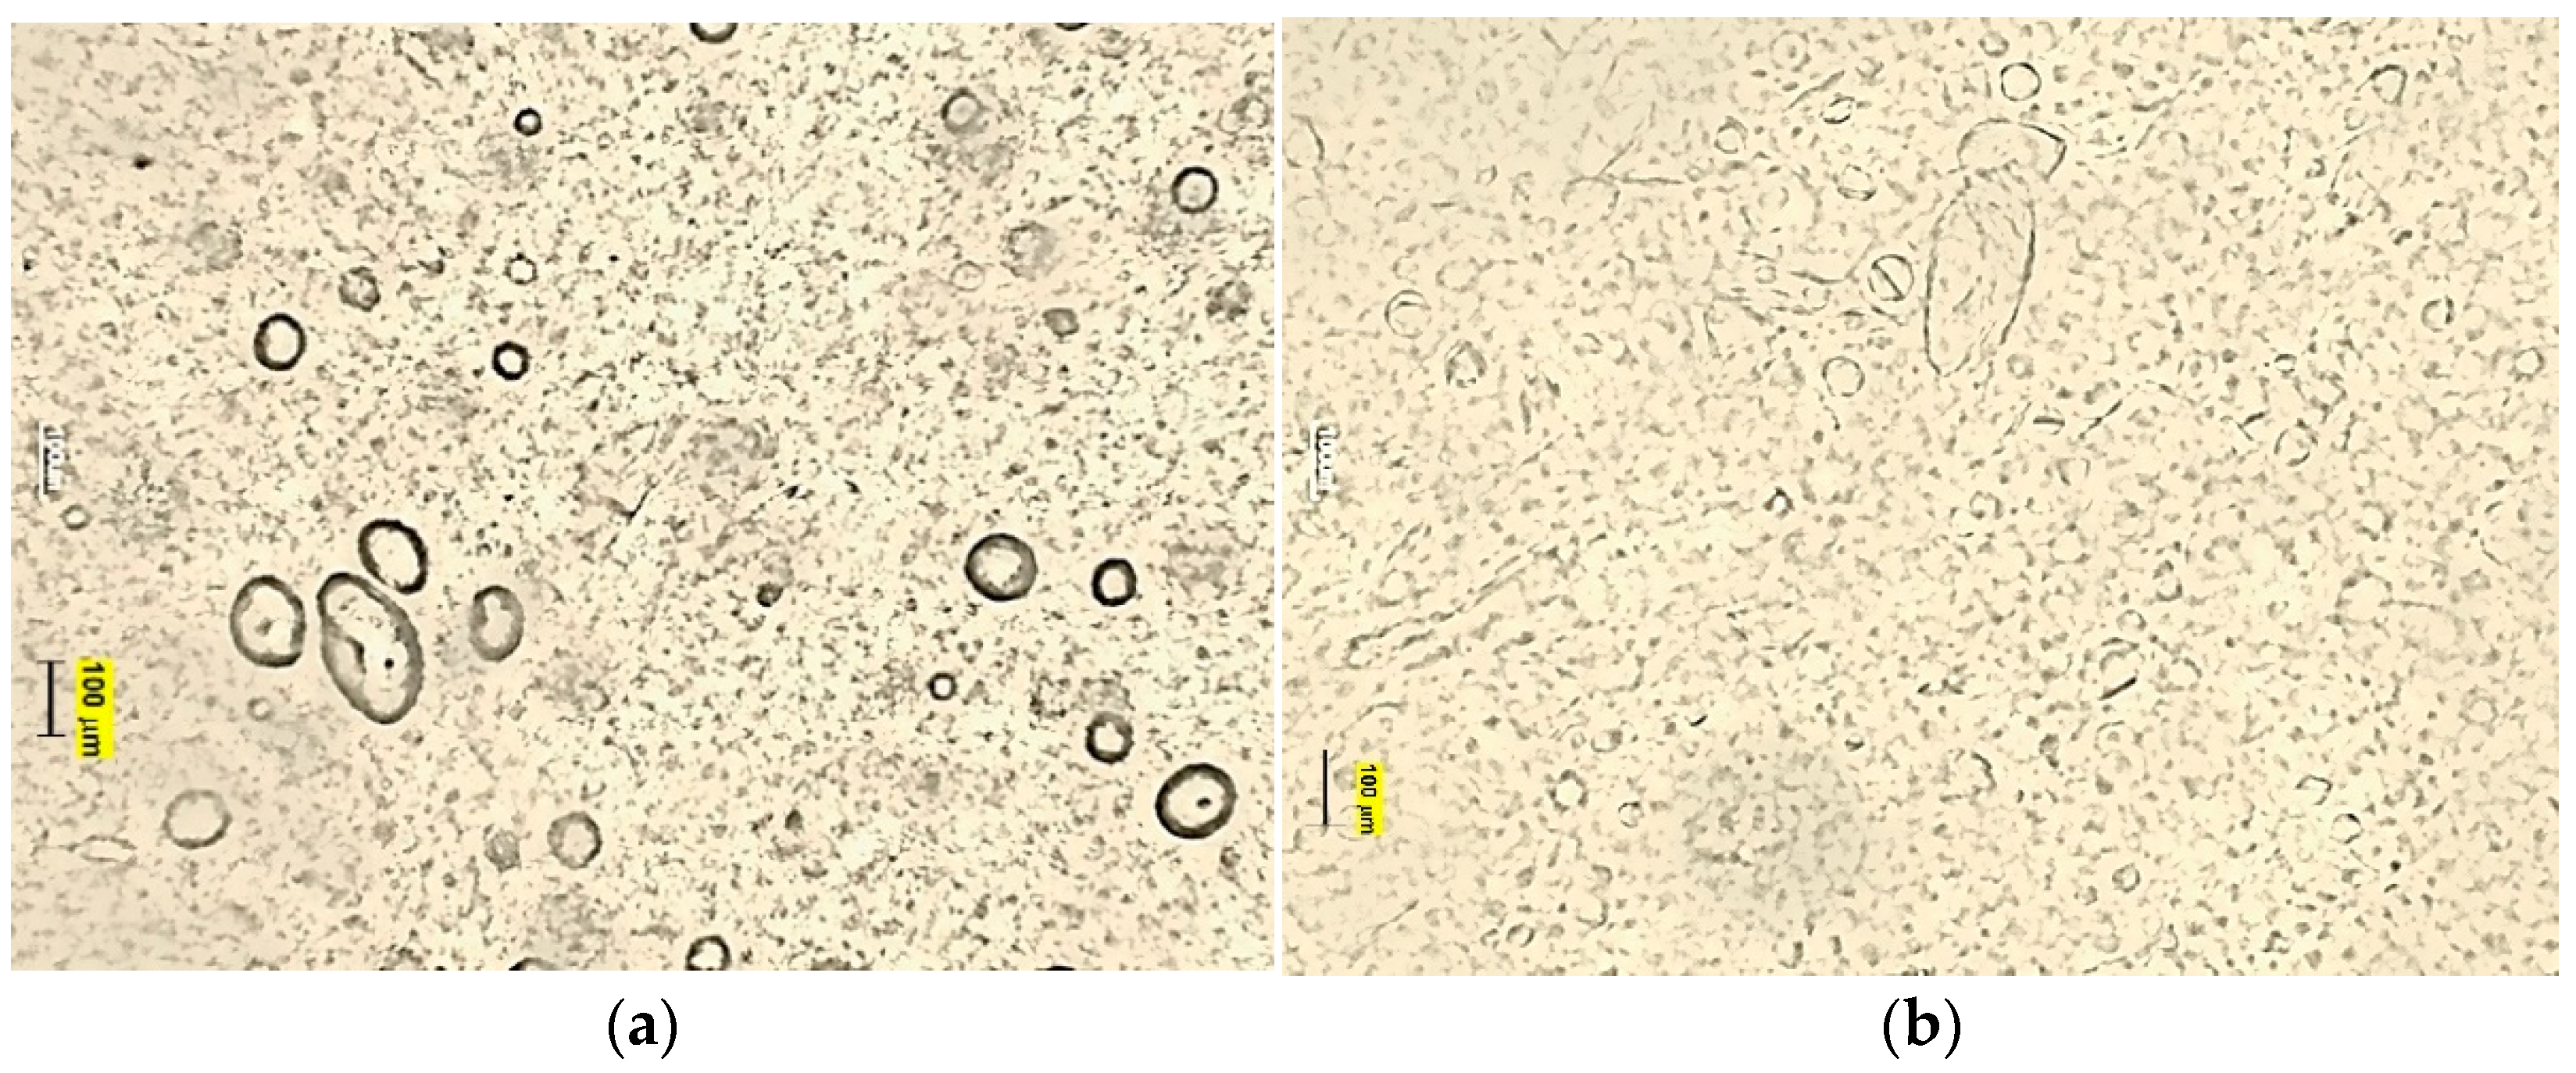

Deep Seated Vesicles In Dyshidrosis Download Scientific Diagram